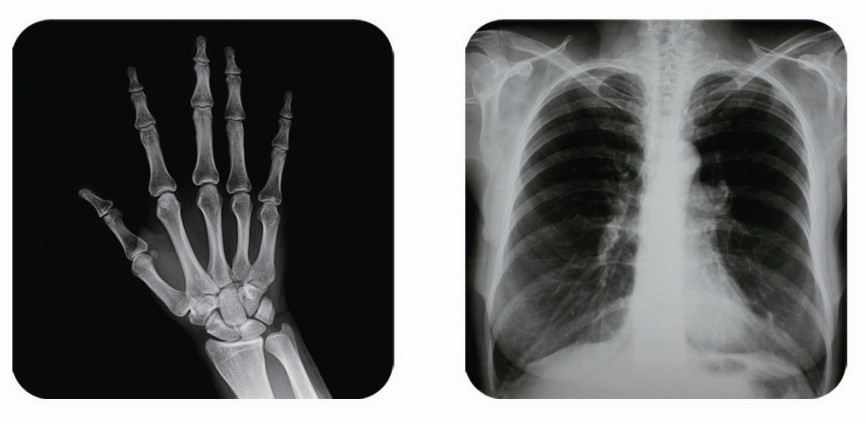

傳統(tǒng)胃腸造影檢查,病變顯示率低,輻射劑量大。普朗醫(yī)療器械公司生產(chǎn)的幾款多功能腸胃造影x光機(jī),更能滿足不同等級不同規(guī)模的大小醫(yī)院選擇,從臨床及科研都很好。尤其最新的PLD8800多功能腸胃造影x光機(jī)用途更為廣泛。多功能腸胃造影x光機(jī)是目前各大醫(yī)院最普及的且用途最廣的一種X光機(jī)。普朗醫(yī)療的胃腸機(jī)功能多,簡便易用,能保證圖像質(zhì)量,該機(jī)采用高制式電視系統(tǒng),優(yōu)秀的數(shù)字化系統(tǒng)能使多功能腸胃造影x光機(jī)的性能得到提高,應(yīng)用范圍獲得極大的拓寬。

1、一般應(yīng)用:數(shù)字透視,動態(tài)及多方位觀察器官病變,圖像更清晰,并可保留末幀圖像;既可使用暗盒完成常規(guī)X線拍片,這是其最大的優(yōu)勢,拍片質(zhì)量大大提高。